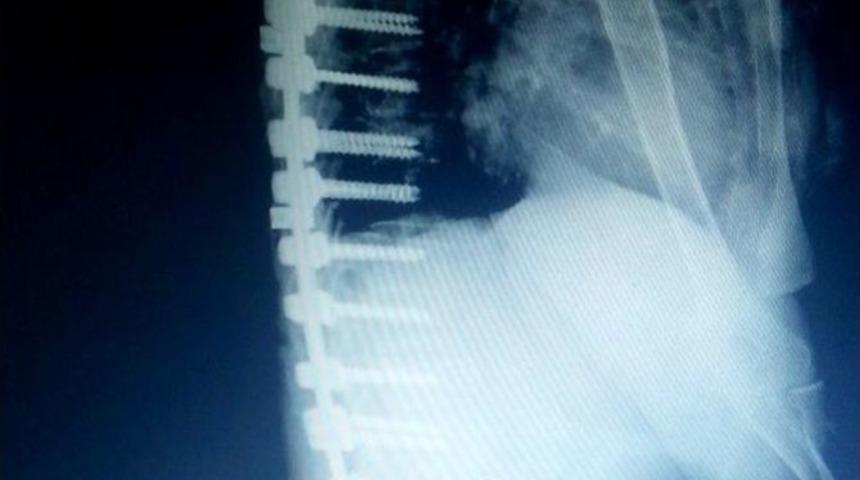

Edremit Devlet Hastanesinde yapılan ameliyatla bir hastaya omurga yapıldı.Şiddetli sırt ve bel ağrısı çektiği, yapılan incelemede kemik erimesine (osteoporoz) bağlı omurga kemiklerinde çökme kırıkları oluştuğu için ağrı olduğunun söylendiğini belirten Şennur Akbulut (53), “Başvurmadığım yer kalmadı. Bana ameliyatın çok riskli olduğu söylenerek felç olabileceğim belirtildi. Çeşitli ameliyatsız tedaviler önerildi. Araştırmalarımda Edremit’te bu tarz ameliyatların yapıldığını, internet üzerinden araştırarak buldum. Muayene için Edremit’e geldim. Ameliyat kararı verildi. Allah’a şükür çok iyiyim, ağrılarım azaldı, şimdi ayakta durabiliyorum. Mutluluğumu anlatamam” dedi.Hasta geldiğinde omurga kemiklerinde çökme nedeniyle kırık oluştuğu ve ağrılarının bunlardan kaynaklandığının görüldüğünü söyleyen Edremit Devlet Hastanesi Beyin ve Sinir Cerrahi Uzmanı Op. Dr. Cengiz Tekin, şunları söyledi:“Hasta bana geldiğinde ayağa kalkmada ve yürümede çok zorlanıyor ve ayakta dik olarak duramıyordu. Yapılan tomografi ve mr sonucunda t6, t9, t12, l1, l2, l3 omurga kemiklerinde çökme ve patlama kırıkları olduğunu gördük. Hastaya operasyonla sırt (torakal) ve bel (lomber) omurgalarına titanyum vida ve plak sistemi ile yeni bir omurga desteği sağlayacağımızı karalaştırdık. Kemik erimesinin ileri derecede olması sırt omurgalarını başlangıcından vida işleminin yapılacağından ileri derecede riskli olduğu aşikardır. Bu durumlarda çok ender olarak operasyon kararı alınabilmektedir. Operasyon 3 saat sürdü. Hastaya 26 titanyum vida ile prod sistemiyle yeni bir omurga desteği sağlayarak hastanın ayakta durmasını ve yürümesini sağlayan yeni bir iskelet destek sistemi oluşturduk. Operasyondan sonraki 3. gününde hastayı yürüttük. Hastanın ve ailenin mutluluğu görülmeye değerdi. 4. günü hastayı taburcu ettim. Tabi henüz her şey bitmedi. Yaranın iyileşmesi ve uygulanan platin ve vidaların kemikle kaynaşması için en az 3 aylık bir zamana daha ihtiyacımız var. Hasta tedavimiz altında ve kontrolümüzde kalmaya devam ediyor.”Tekin, “Bursa merkezinden böyle büyük ve riskli ameliyat için hastamızın Edremit Devlet Hastanesini tercih etmesi ve bize güvenmesi bizim gurur kaynağımız oldu. Hastanın ve ailenin mutluluğu bizi daha çok sevindirdi” şeklinde konuştu.